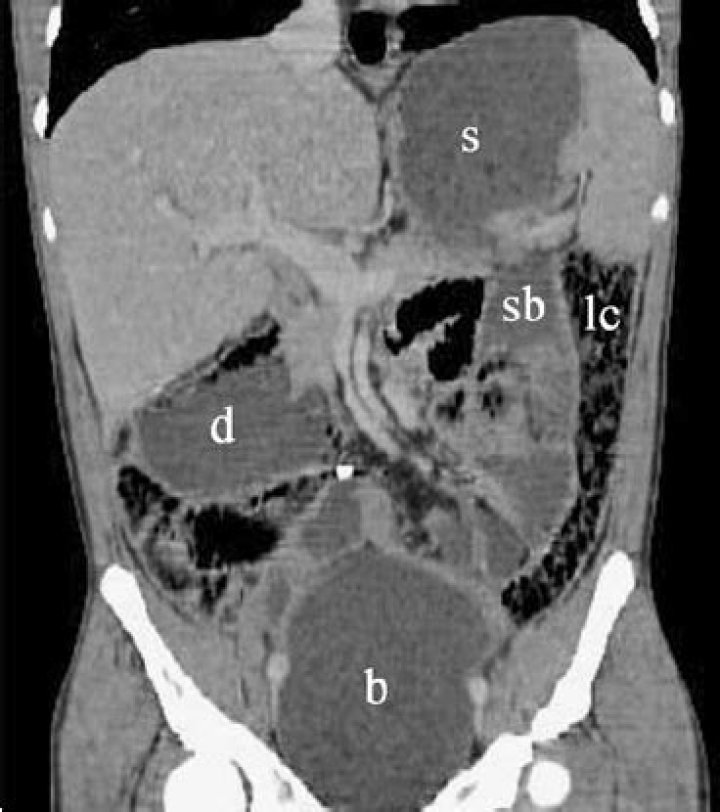

Chronic intestinal pseudo-obstruction (CIPO) is a rare disease characterized by repetitive episodes or continuous symptoms of bowel obstruction when no blockage exists.

Chronic intestinal pseudo-obstruction (CIPO) is a rare gastrointestinal motility disorder characterized by recurring episodes resembling mechanical obstruction in the absence of organic, systemic, or metabolic disorders, and without any physical obstruction being detected by X-ray or during surgery.